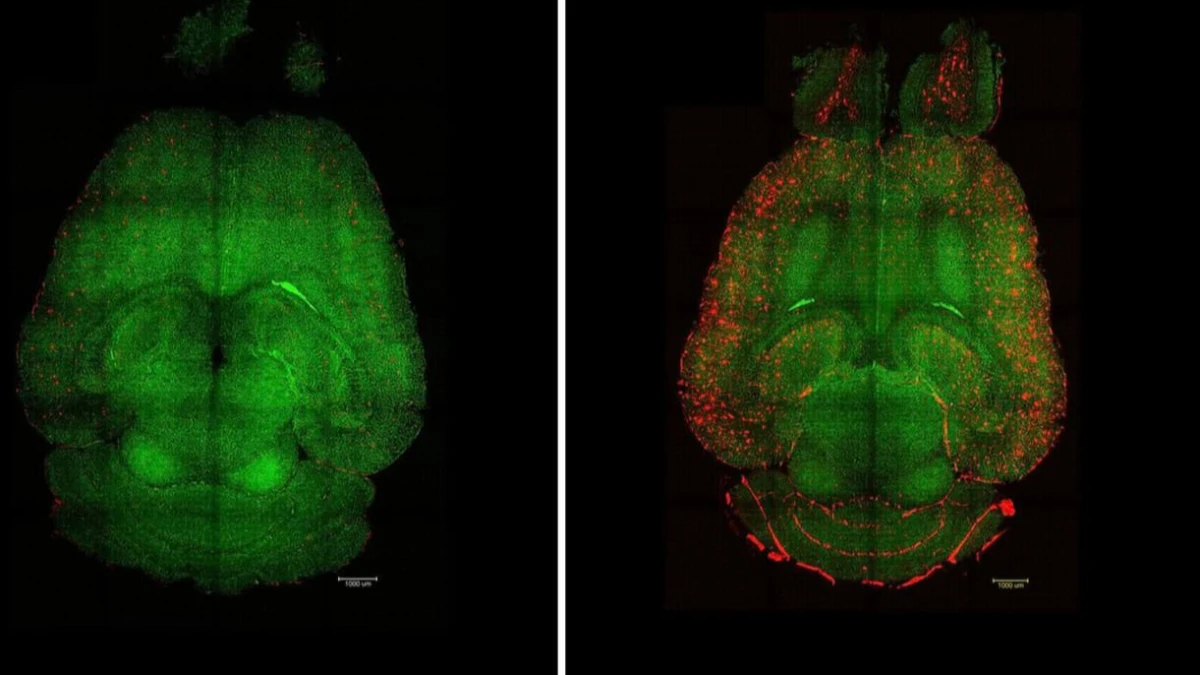

Nanoteknoloji temelli bir strateji, Alzheimer benzeri patolojiye sahip farelerde hastalığı tersine çevirmede umut verici sonuç verdi. Çalışma, yalnızca taşıyıcı olmayan, kendi başına terapötik etki gösteren yeni bir nanopartikül sınıfını, yani ‘supramoleküler ilaçları’ tanıtıyor. Katalonya Biyomühendislik Enstitüsü (IBEC) ile Sichuan Üniversitesi Batı Çin Hastanesi (WCHSU) ortaklığındaki ekip, yaklaşımın nöronları doğrudan hedeflemek yerine beynin damarsal bekçisi kan-beyin bariyeri (BBB) üzerinden etki ettiğini vurguluyor.

Beynin yüksek enerji ihtiyacı, oksijen ve atık uzaklaştırma için hassas bir damar ağına bağlı. Alzheimer’da bu ağ ve özellikle BBB bozuluyor; bunun sonucu amiloid-beta (Aβ) gibi toksik proteinler birikiyor ve nöronal işlev zarar görüyor. Araştırmacılar, Aβ aşırı üretimi ve bilişsel gerileme gösteren fare modellerinde, boyutu ve yüzey ligandları hassas tasarlanmış nanopartikülleri yalnızca üç doz uyguladı; ilerleme düzenli olarak izlendi.

Ekip, enjeksiyondan bir saat sonra beyindeki Aβ seviyelerinin yüzde 50–60 düştüğünü raporladı. Etkinin kısa sürede başlaması, supramoleküler ilaçların BBB üzerinden Aβ temizliğini tetiklediğine işaret etti. Nanopartiküller, BBB’nin geçiş kapılarından biri olan LRP1 proteiniyle etkileşecek şekilde tasarlandı; LRP1 ligandlarını taklit ederek Aβ’ye bağlandılar ve onu bariyerden kana taşıyan doğal boşaltım yolunu yeniden devreye soktular.

Tedavinin en çarpıcı bulgusu, uzun dönem etkiler oldu. 12 aylık (yaklaşık ‘60 yaş’ insan karşılığı) farelere uygulanan nanopartiküller, 18 aya (yaklaşık ‘90 yaş’) kadar izlenince, hayvanların hafıza ve davranış profilinin sağlıklı ve genç farelere yakınsadığı görüldü. Araştırmacılar, bunun damar sisteminin onarımıyla bir kısır döngünün kırılmasından kaynaklandığını belirtiyor: BBB düzgün çalıştığında Aβ ve diğer toksinlerin temizliği yeniden hızlanıyor, hastalığın ilerlemesi duruyor ve beyin sistemi denge durumuna geri dönüyor.

Derinlemesine analizler, supramoleküler ilaçların LRP1’i yeniden aktive eden bir ‘anahtar’ gibi davrandığını ortaya koydu. Normal koşulda LRP1, Aβ’yi bağlayıp BBB’den dolaşıma taşıyarak uzaklaştırıyor; Alzheimer’da bu mekanizma tıkanıyor. Nanopartiküller, LRP1’in doğal ligandlarına benzer şekilde Aβ’yi hedefleyip taşıma sürecini başlatıyor; böylece damarlar yeniden etkili bir atık temizleme yolu haline geliyor.